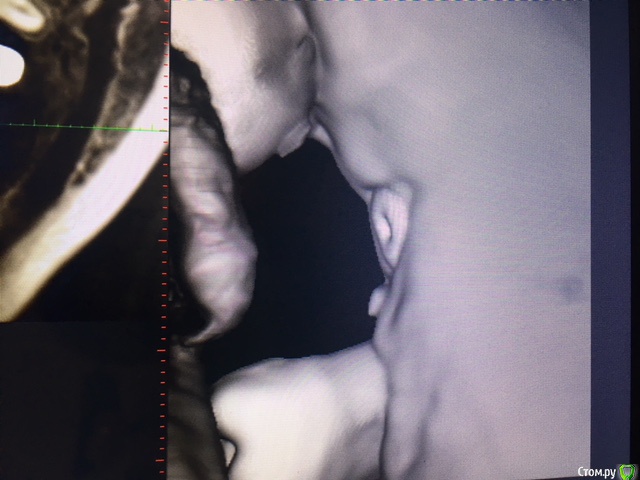

evaverkina Опубликовано 22 февраля, 2018 Автор Поделиться Опубликовано 22 февраля, 2018 (изменено) Фото КТ Изменено 22 февраля, 2018 пользователем evaverkina Ссылка на комментарий

evaverkina Опубликовано 22 февраля, 2018 Автор Поделиться Опубликовано 22 февраля, 2018 Сделайте Кт Фото КТ прикрепила, есть возможность отправить вам КТ целиком или этого достаточно? Ссылка на комментарий

red_butler Опубликовано 22 февраля, 2018 Поделиться Опубликовано 22 февраля, 2018 Зуб не травмирован Ссылка на комментарий

Bier Опубликовано 23 февраля, 2018 Поделиться Опубликовано 23 февраля, 2018 По КТ все хорошо. Ссылка на комментарий